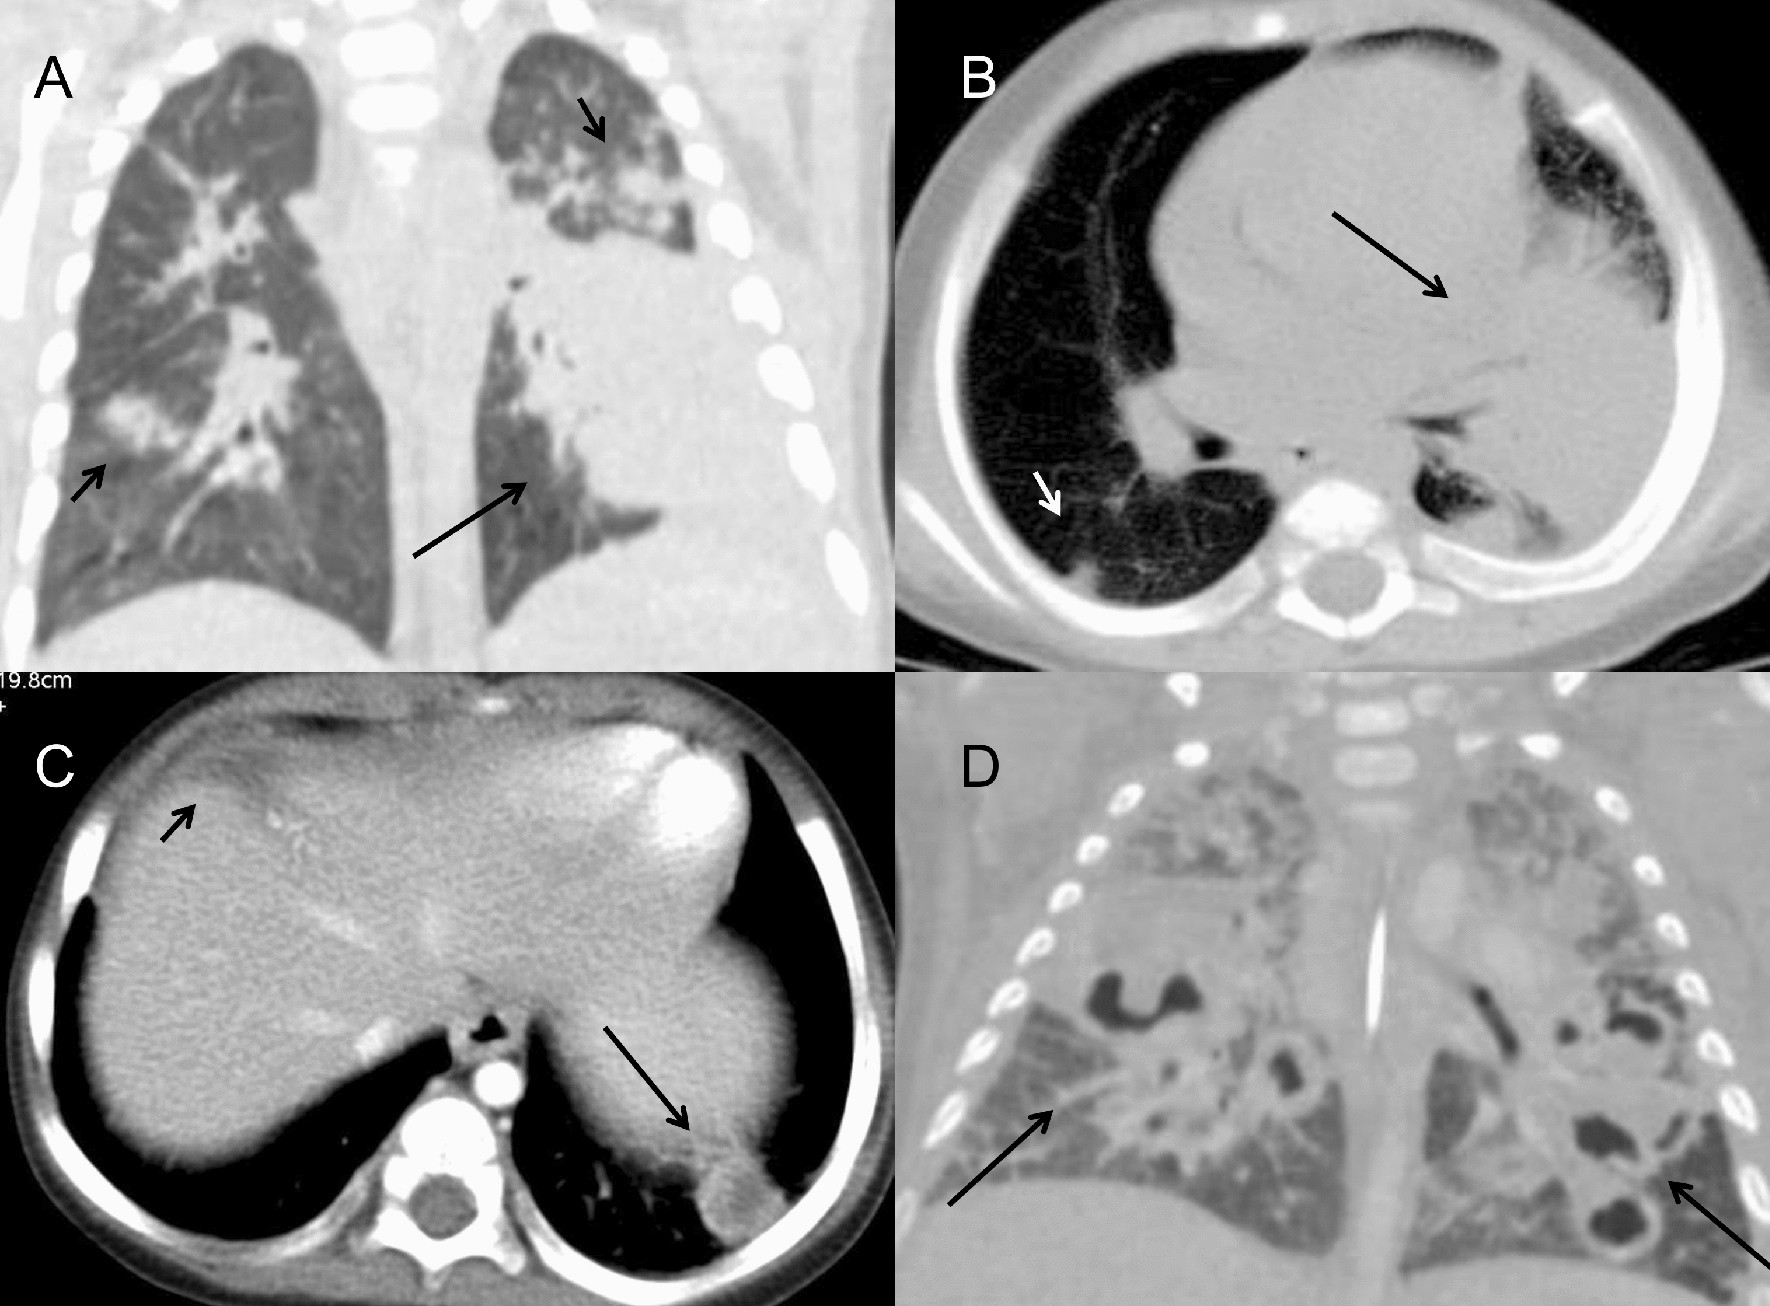

Figure 4

Bacterial infection in CGD patients. (A,B) A 5-month-old boy with klebsiella pneumoniae infection showed a large area of consolidation in the left lower lobe on axial and coronal reformat CT images (long arrow). Multiple nodular lesions in the bilateral lung fields were found (short arrow). (C) A 1-year-old boy with Staphylococcus aureus infection. Chest CT showed the small nodular lesion with abscess inside in left lower lobe (long arrow). The low-attenuated lesion in the left lobe of liver was seen, suggesting the possibility of hepatic abscess (short arrow). (D) A 1-year-old boy with Staphylococcus aureus infection. On CT, masses and patchy consolidations were found in the bilateral lung fields with multiple small cavities formation (long arrow).